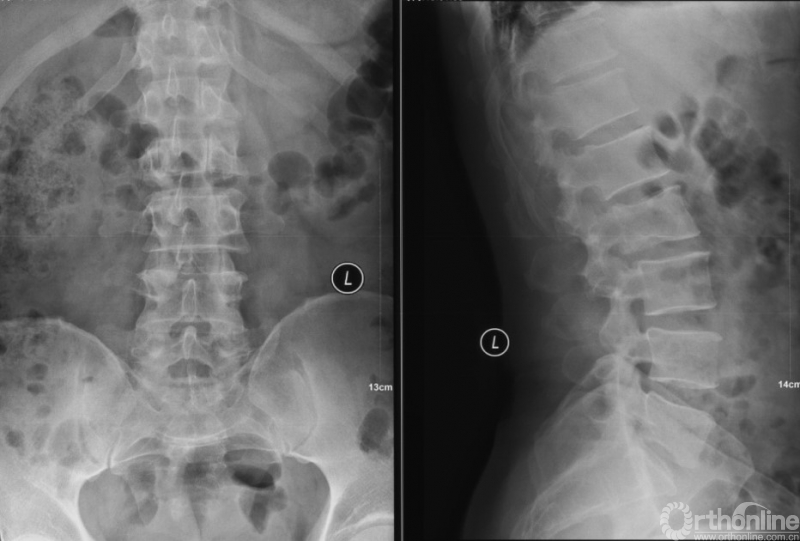

PVP治疗

术后6个月

经Spine Oncology Study Group(SOSG)评估硬膜外脊髓压迫(ESCC)为Grade 1a型,轻度脊髓压迫;脊柱机械稳定性评估(SINS)7分,中度不稳。修正Tokuhashi评分(RTS)6分,预计生存<6个月,建议姑息性手术及保守治疗;结合Tomita评分系统6分,故行姑息性手术短期控制。